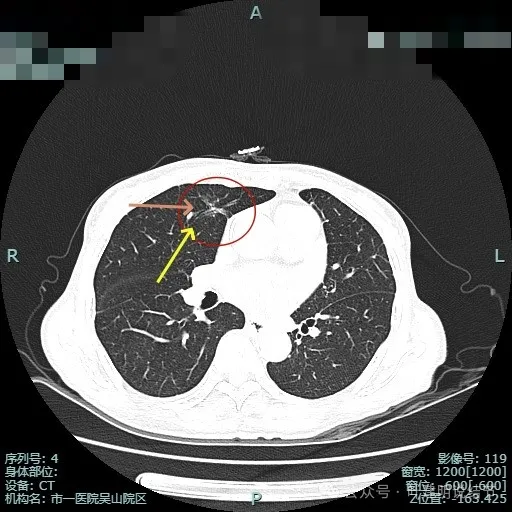

再看2024年10月在杭州市肿瘤医院复查的影像:

病灶出现,表面不平分叶状,有异常增粗血管贴着病灶,整体轮廓较清,看着非常不舒服。

毛刺明显,灶内小血管走行,表面分叶,轮廓清楚,瘤肺边界清。